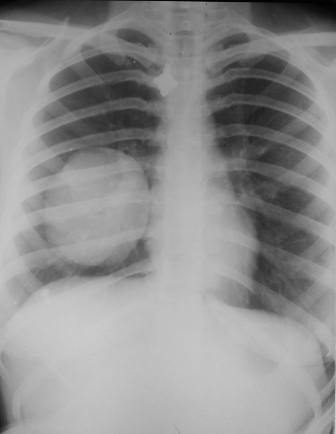

Rx toracică, incidență P-A

DESCRIERE:

la niv. întregului hemitorace drept → opacitate extinsă, nesistematizată, de intensitate mare, omogenă

caracter expansiv → împinge traheea și mediastinul de partea opusă

diafragm deplasat în jos

lărgirea spațiilor intercostale

umplerea spațiului costo-diafragmatic

DX: pleurezie masivă

DD: atelectazie → caracter retractil